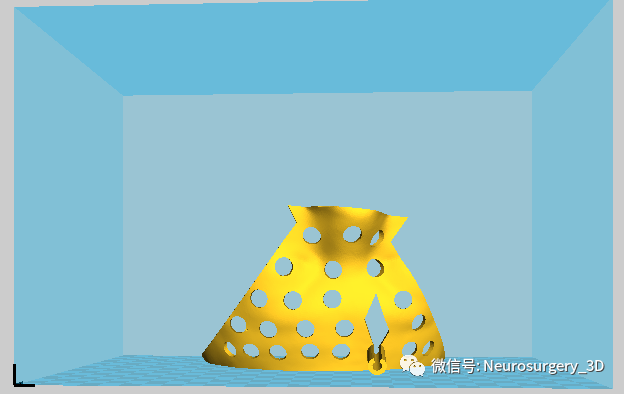

11、穿刺导板镂空:把Mimics剪切后的导板导入E3D软件界面,进行镂空处理后备用。